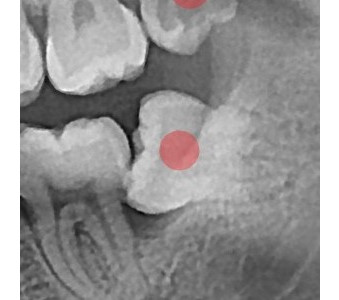

以成果证明实力。

国际摩牙齿科

真实临床案例